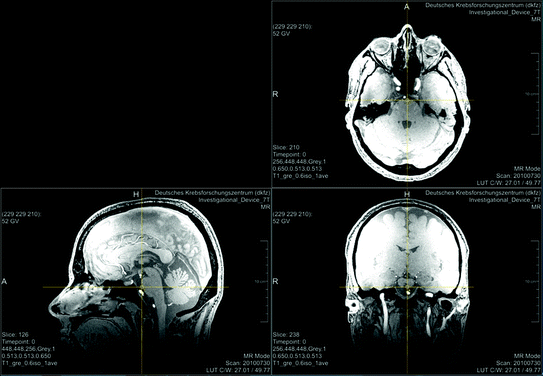

Even if an infrastructure is provided that enables the filtering of data described above, you will always have medical data that is easily reidentifiable and at least hard to be pseudonymized. Good examples are radiological head or whole body images. Figure 1 shows head images from a study participant.20 The original perspective of the image (axial view) and the other medical perspectives (sagittal and coronal view) may not be suitable for reidentification by everyman. But a simple volume rendering of the data (Fig. 2) allows easy reidentification. Starting from this point with modern technologies several scenarios are not too far-fetched. An artificial picture, for instance, could be reconstructed and used with available face recognition APIs21 or you could take the volume data convert it into a 3D model and print it via a 3D-printer.22

Fig. 1

Example for a magnetic resonance head image (MRI). The upper MRI shows an original layer of data set of an study participant (axial view, parallel to the feet). The MRIs below are reconstructions of the original data in sagittal view (left) and coronal view (right). The sagittal view is similar to a head silhouette and therefore more familiar